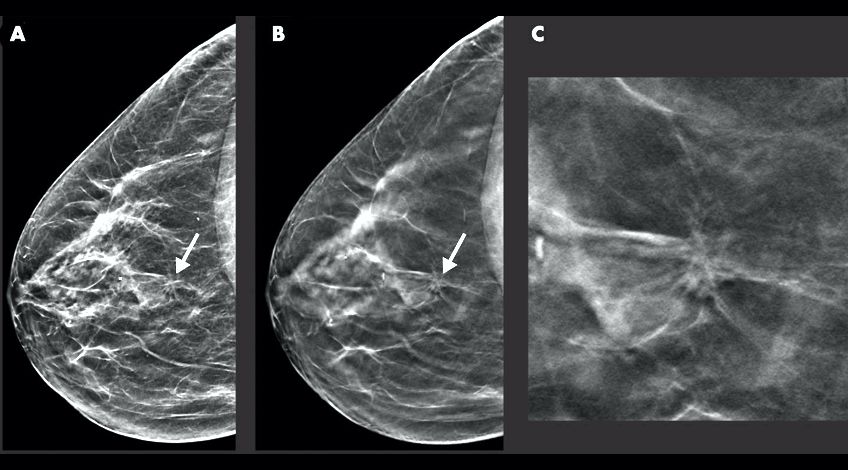

La Organización Mundial de la Salud (OMS) recomiendan realizar una mamografía de diagnóstico de forma regular para detectar el cáncer o cualquier anomalía de manera oportuna. En Chile una de las causas de muerte más frecuentes entre las mujeres es el cáncer de mama.

En Clínica Altacura, ubicados estratégicamente en el corazón de Concepción, en Ohiggins 1250 (a solo dos cuadras del Mall del Centro), te brindamos la mamografía, el examen radiológico esencial para una detección temprana y efectiva del cáncer de mama, avalado por la OMS. Invierte en tu bienestar y gana la tranquilidad de cuidarte en el centro de tu ciudad.